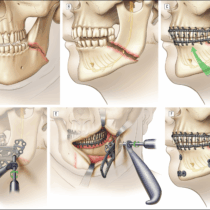

Orthognathic Surgery

Corrects skeletal misalignments, improving chewing function and facial profile.

Personalized Approach